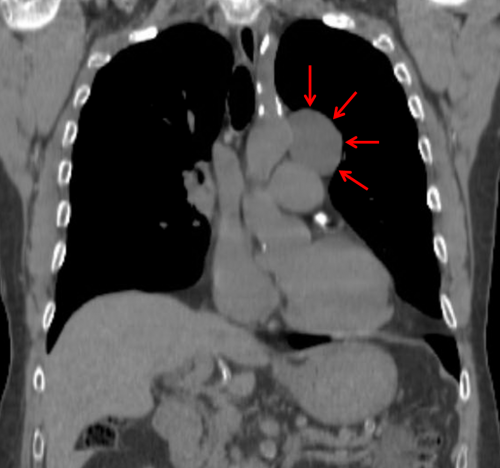

Age: 55

Sex: Male

Indication: Chest pain

Sample ReportLeft middle mediastinal mass. Recommend CT for further evaluation.